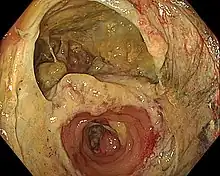

A hand-sewn bowel anastomosis, in this case of the sigmoid colon